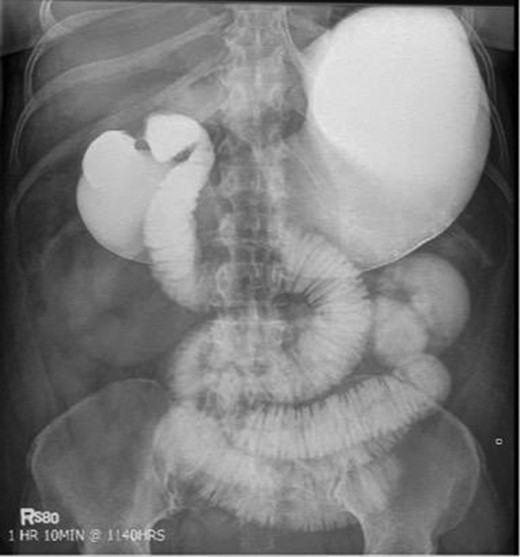

Laboratory studies were remarkable for leukocytosis, and an elevated lactate that improved with hydration (Fig. 1), while urinalysis was unremarkable. Abdominal CT scan obtained at this time demonstrated a partial SBO in the mid-small bowel as well as inflammation and thickening of the duodenum. A small bowel series was ordered, and showed high grade SBO (Figs 2–5).

Fluoroscopic barium study demonstrating oral contrast agent progression through the small bowel at 1 h after ingestion. The stomach is distended, with dilated bowel loops throughout the abdomen.